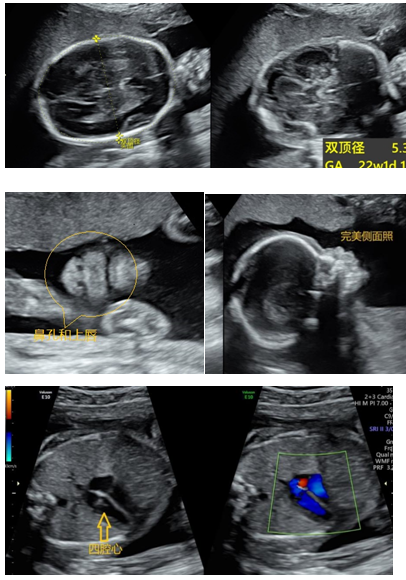

孕20-26周TA已经长得有模有样,系统结构清晰,头身大小合适,明显长壮实了。超声检查时会看到你的宝贝在羊水里自“游”自在,或打个哈欠,或伸伸懒腰,或翻身躲藏,或手舞足蹈。孕20-26周是超声检查胎儿解剖结构和筛查胎儿畸形(大排畸)最适宜的时间,可以见证TA的颅脑结构、颜面部、颈部、肺、心脏、肝胆、胃肠、肾脏、膀胱、脊柱、四肢等结构(图片6-1、图6-2)。胎儿这些系统和器官结构的检查,是超声医生通过慧眼观察和巧手找寻,最终在上百个超声切面上实现的。上述检查为我们提供了如此美妙的胎儿图像,同时保障了优生优育,不禁感慨小小超声大大能量!

图6-1 超声显示:中孕